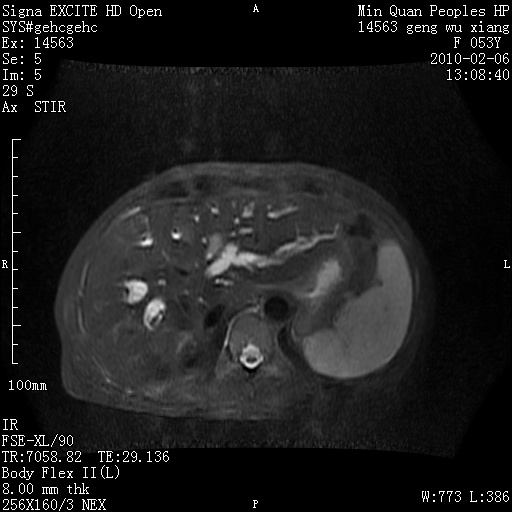

标题: MRI2762:胆道梗阻原因?

f,53y,全身黄染多日。

高位胆道梗阻 胆管癌可能性大

支持 高位胆道梗阻 胆管癌可能性大。